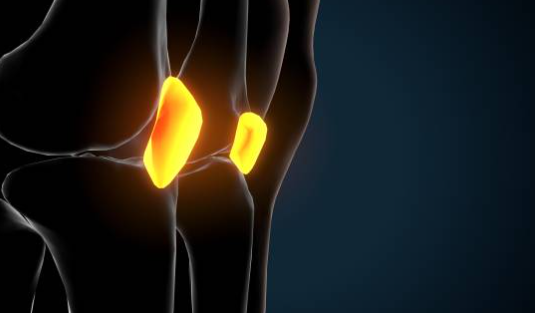

내측 반월상 연골은 무릎 관절의 쿠션 역할을 하며, 충격을 흡수하고 관절의 움직임을 돕습니다. 내측 반월상 연골이 찢어지거나 파열되면 무릎 안쪽 통증이 발생하며, 부기, 무릎의 잠김 현상, 관절의 움직임 제한 등의 증상이 동반될 수 있습니다. 내측 반월상 연골 손상은 스포츠 활동 중에 갑자기 방향을 바꾸거나 점프하는 경우에 자주 발생합니다.

퇴행성 반월상 연골 파열은 나이가 들면서 반월상 연골이 약해지고 손상되는 질환입니다. 퇴행성 반월상 연골 파열이 발생하면 무릎 안쪽 통증이 발생하며, 부기, 무릎의 잠김 현상, 관절의 움직임 제한 등의 증상이 동반될 수 있습니다. 퇴행성 반

월상 연골 파열은 특별한 외부 요인 없이도 발생할 수 있으며, 나이가 들수록 더 많이 발생합니다.

내측 콘드롬은 무릎 안쪽의 연골이 마모되어 관절의 안정성이 떨어지는 질환입니다. 내측 콘드롬이 발생하면 무릎 안쪽 통증이 발생하며, 부기, 무릎의 불안정감, 관절의 움직임 제한 등의 증상이 동반될 수 있습니다. 내측 콘드롬은 과도한 운동, 비만, 외상 등의 요인으로 인해 발생할 수 있습니다.